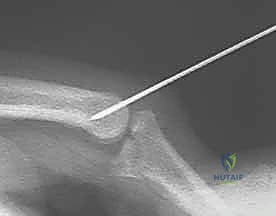

The patient is positioned supine on the operating table with the operative extremity extended on a radiolucent hand table. A well-padded proximal arm tourniquet is applied. Intravenous regional anesthesia (Bier block), regional brachial plexus block, or general anesthesia may be utilized depending on patient comorbidities and anticipated surgical duration. The arm is prepped and draped in standard sterile fashion. Intraoperative fluoroscopy must be available and positioned to allow dynamic, real-time assessment of the radioulnar relationship and impingement following resection.

The arm is then taken through a full, dynamic range of motion under direct visualization and fluoroscopy. The surgeon must palpate the radioulnar interval to ensure no point-loading or impingement occurs at any extreme of rotation. If impingement is noted, further contouring of the ulnar stump is performed iteratively until smooth, frictionless tracking is achieved.